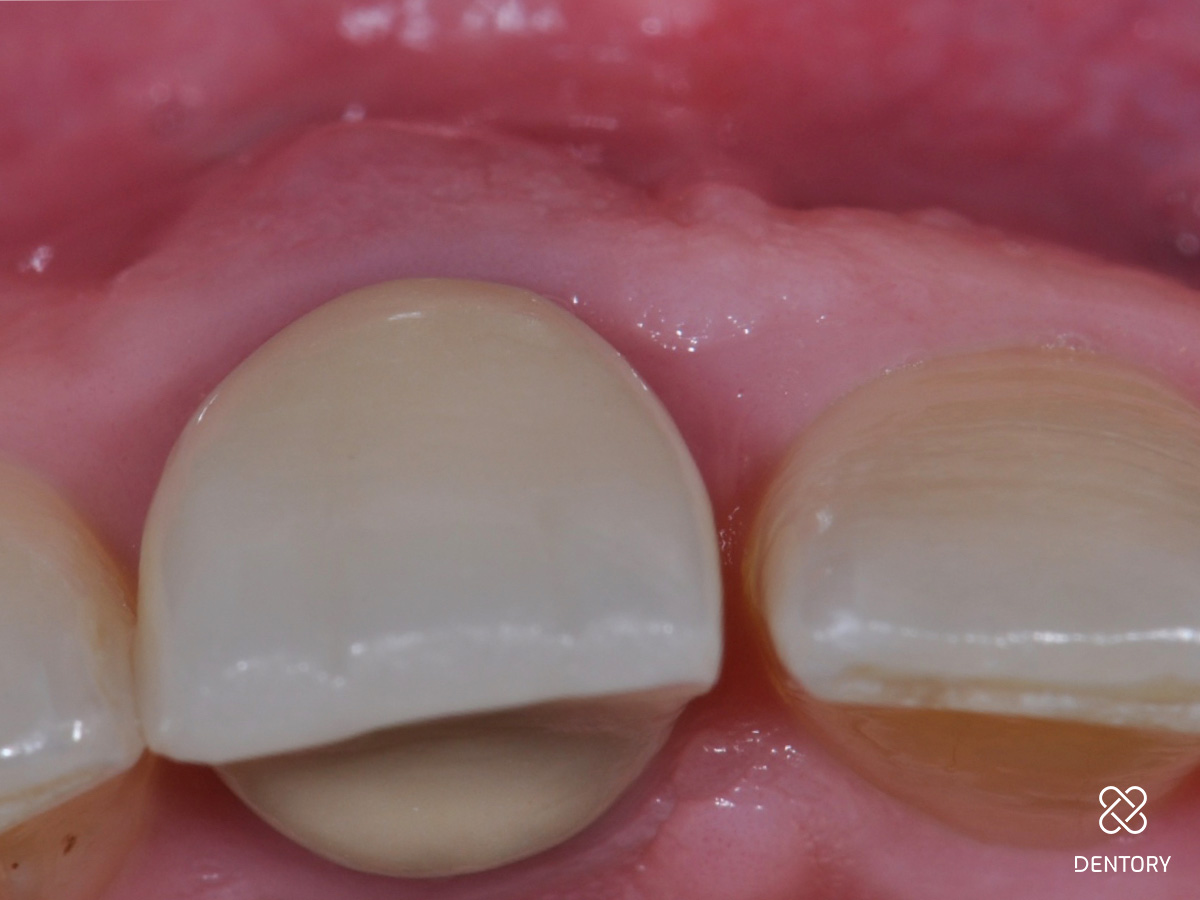

Abbildung 1

Ausgangssituation: Frontalansicht.

Abbildung 2

Der überkronte Zahn 11 ist elongiert und zeigt deutliche Entzündungszeichen mit einer vestibulären Schwellung.